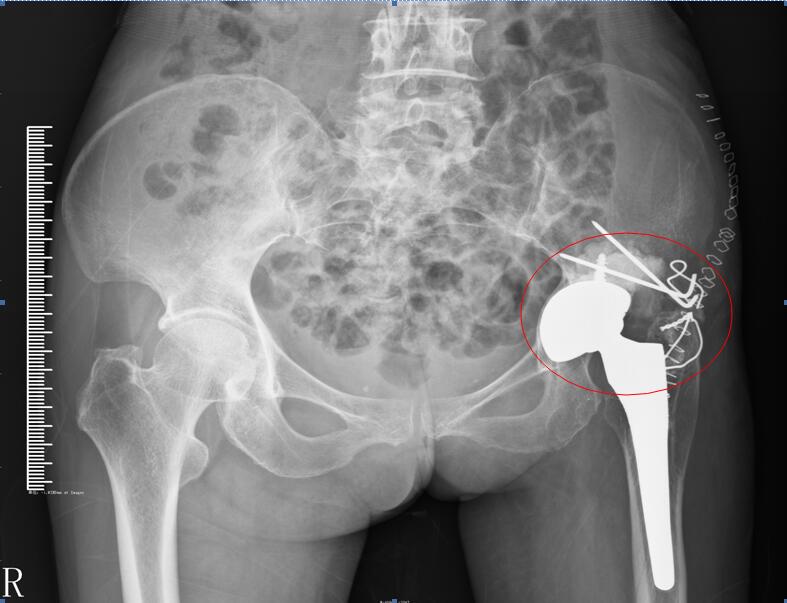

“万事开头难”,类似的手术鲜有先例。邹本国主任和他的医疗团队便开始查阅大量文献资料,并向国内一线专家请教。最终确定为全女士开展“骨盆肿瘤扩大切除+钢针骨水泥技术再造髋臼术”。韩键主治医师首先在CT下为病人髋臼肿瘤位置做了精准穿刺活检,为手术打下良好的基础。此后,医疗团队对患者的肿瘤部位进行了扩大切除,切掉大部分髋臼,而这个部位又是身体负重最大的一个部分。对此,他们又用骨水泥给患者再造了一个人工髋臼,为了保障它的稳定性,还用钢针对其进行固定。术后拍片显示,关节假体以及再造髋臼位置良好,两者结合牢固。没过几天,全女士就能借助拐棍下床行走。邹主任说:“再过三个月,患者就能扔掉拐棍,像正常人一样行走了。这样的手术,在省内尚属首例。手术不但减轻了患者身体上的痛苦和心理负担,更重要的是给她树立了生活的信心。它给予我们一个很好的启示,今后再有类似的病症我们就能更好地科学应对。”

(图中标注为手术开展部位)